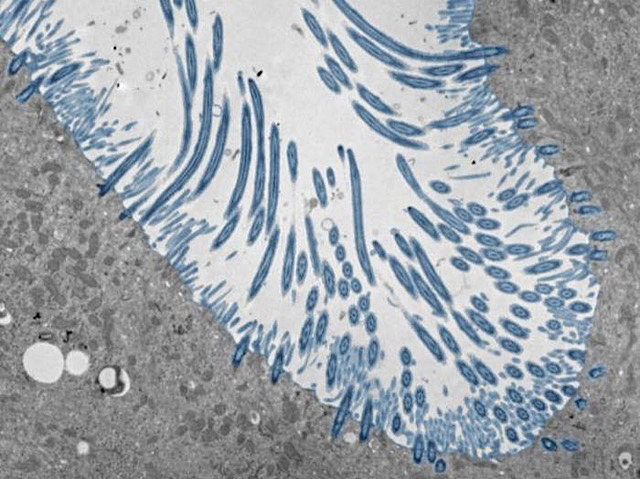

Refredar-se pot provocar quasi cap símptoma en algunes persones, mentre que en altres pot causar una malaltia respiratòria greu. Per a investigar com es generen resultats tan diferents, els científics han estudiat la resposta a la infecció en organoides d’epiteli nasal humà (a la imatge): un conjunt de tipus cel·lulars derivats de cèl·lules mare nasals, que inclouen cèl·lules productores de mucositat i cèl·lules amb cilis (de color blau). Utilitzant rinovirus, la causa més freqüent dels refredats, els investigadors van observar que, quan els organoides produïen, de manera ràpida i robusta, la citocina interferó, limitaven eficaçment la replicació i la propagació del virus. En canvi, una producció deficient d’interferó, o una càrrega viral elevada, feia que les cèl·lules produïren altres citocines proinflamatòries i grans quantitats de moc. El treball mostra com la resposta de l’hoste, més que el virus en si, pot influir en la progressió de la malaltia, i assenyala possibles vies i citocines que podrien ser objecte de teràpies per a afavorir una resposta antiviral saludable.